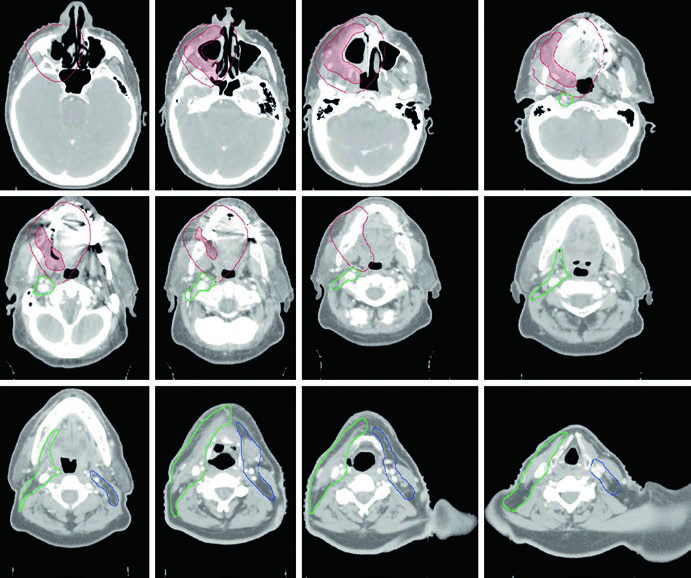

Caso Clínico: Trígono Retromolar T4aN2b

La Figura 6.3 demuestra un CEC de trígono retromolar, T4aN2b, con compromiso del pterigoideo medial, post-resección con enfermedad residual macroscópica y vaciamiento cervical derecho. El CTV70 (rojo sombreado) se delinea basándose en los hallazgos operatorios y las imágenes pre y postoperatorias.

El CTV59,4 se muestra en rojo (región tumoral) y verde (cuello ipsilateral). El CTV54 (azul) incluye los niveles IB a IV contralaterales.

La fosa pterigopalatina funciona como puerta de entrada para la diseminación tumoral hacia la fosa craneal media. Su cobertura adecuada es esencial cuando existe invasión del músculo pterigoideo. Los volúmenes postoperatorios deben incluir todo el lecho quirúrgico, utilizando la inflamación y edema tisular en la TC de planificación para delimitar las áreas de manipulación quirúrgica.

Caso Clínico: Encía T4aN1 con Invasión Ósea

La Figura 6.4 muestra un CEC de encía, T4aN1, con invasión ósea, post-resección con mandibulectomía marginal y vaciamiento cervical izquierdo. El CTV66 (rojo) cubre la región de invasión ósea. El CTV60 (verde) incluye todo el lecho operatorio y los niveles I a IV ipsilaterales.

El CTV54 (azul) abarca los niveles I a IV contralaterales. La decisión de incluir el cuello contralateral se basó en la enfermedad ganglionar positiva (N1) y el estadio T4 — ambos factores que elevan el riesgo de compromiso contralateral. En tumores de encía bien lateralizados con estadificación más favorable, esta cobertura podría omitirse.

Caso Clínico: Mucosa Yugal T2N3b con Extensión Extranodal

La Figura 6.5 presenta un CEC de mucosa yugal, T2N3b, post-resección con vaciamiento cervical derecho y extensión extranodal en el nivel IB. Márgenes negativos pero próximos en el margen profundo. El CTV66 (rojo) cubre la región ganglionar con extensión extranodal.

El CTV60 incluye el lecho operatorio y toda la mucosa yugal, con niveles I a IV ipsilaterales. El CTV se extiende cranealmente hasta el surco vestíbulo-gingival y fosa infratemporal a la altura del reborde orbitario inferior, caudalmente hasta el surco vestíbulo-gingival y glándula submandibular, anteriormente hasta la comisura labial, y posteriormente hasta el trígono retromolar. Se necesitan márgenes amplios incluso para tumores primarios menores. Se coloca bolus cutáneo para cobertura adecuada de los CTVs de alto e intermedio riesgo.

El CTV54 incluye los niveles I a III contralaterales, debido a la extensión de la enfermedad ganglionar en el cuello ipsilateral. Este caso ilustra cómo la presencia de extensión extranodal amplía significativamente los volúmenes de tratamiento necesarios.

Caso Clínico: Piso de Boca T4aN2b

La Figura 6.6 demuestra un CEC de piso de boca, T4aN2b, con invasión mandibular, post-hemimandibulectomía derecha y vaciamiento cervical bilateral. El CTV66 (rojo) abarca el área de extensa invasión ósea. El CTV60 (verde) incluye todo el lecho operatorio y los niveles I a V en el lado ipsilateral.

El espacio retroestiloideo ipsilateral se incluye en el CTV60 como área de alto riesgo para metástasis ganglionar, especialmente con compromiso del nivel II. El CTV60 también se extiende para incluir todo el complejo del piso de boca. El CTV54 (azul) incluye los niveles I a IV contralaterales.